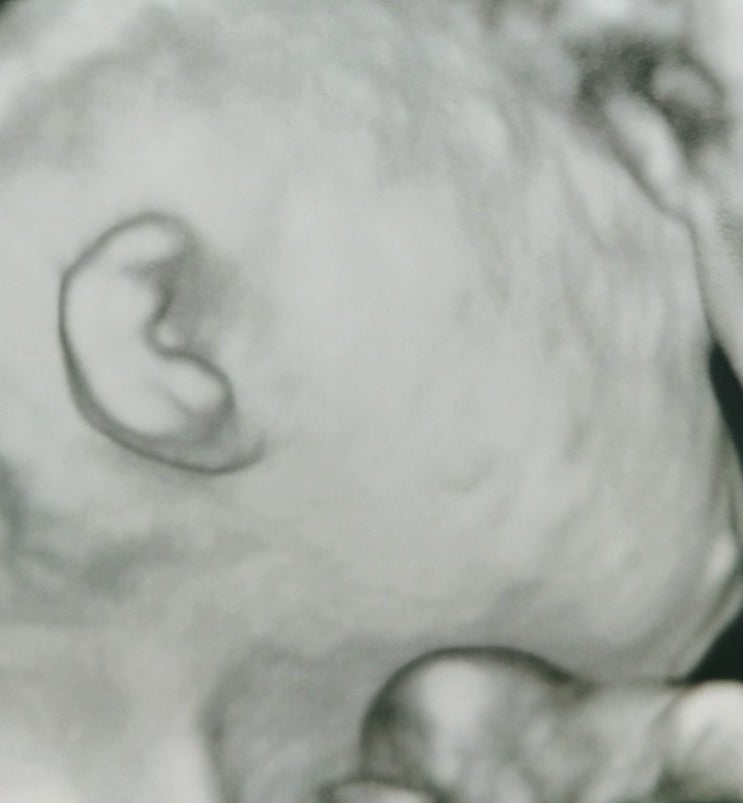

임산부 커피.하루 카페인량♥

ㅋㅋㅋㅋㅋ둘째를 대비하여 남기는 커피정보 왜냐면..난 커피없음 못사니께...ㅠㅠ 산부인과 쌤마다 다르긴...